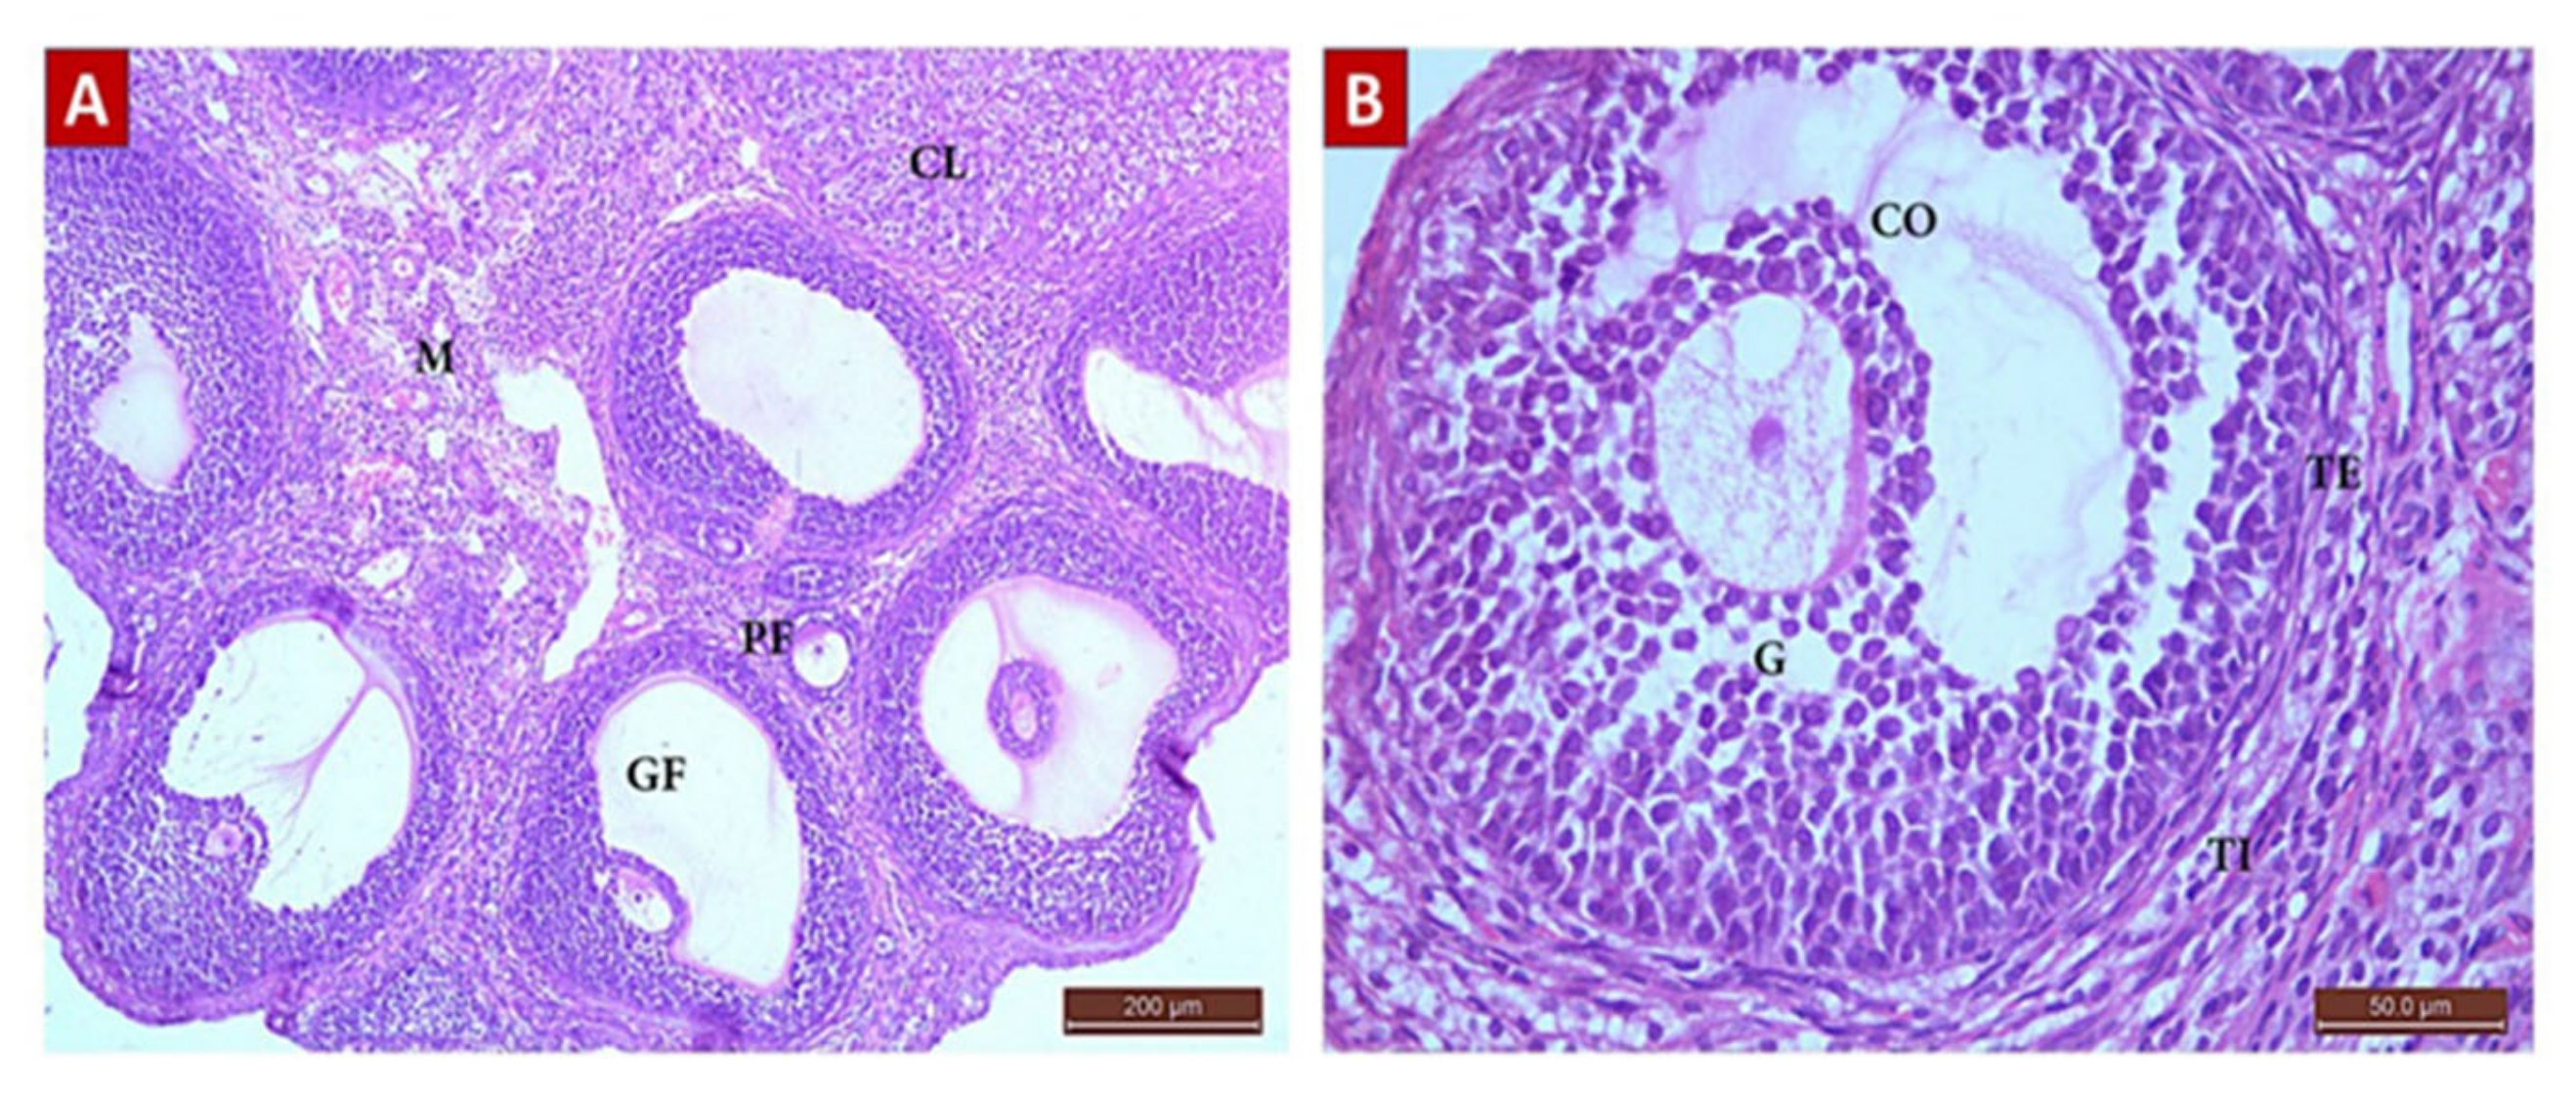

Diosmin 100 (Group IV, Figure 7)